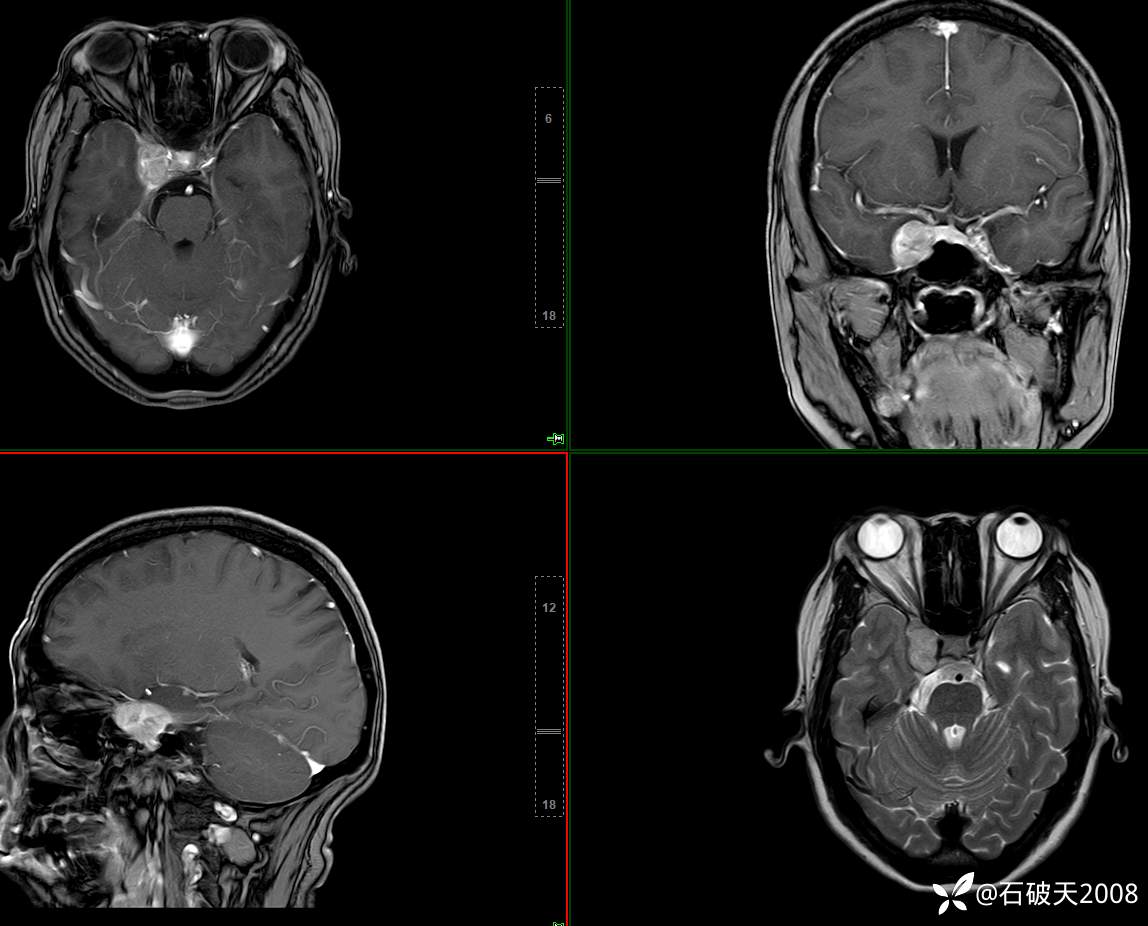

鞍旁占位,相信讨论区会有两种判断(病理已公布)

胡志勇HZY 达人已点赞女 48岁 主 诉:头晕、右眼复视1月余。

现病史:患者1月前无明显诱因出头晕、右眼视物复视、重影;向右侧视物时明显,余方向及左眼视物无特殊不适,头晕为非旋转性,不伴随体位变化;无恶心、呕吐、胸闷、肢体言语活动不利症状;为行系统治疗来院门诊“颅内占位性病变”收住院。发病来患者神志清,精神差,饮食睡眠可,大小便正常,体重无下降。

增强